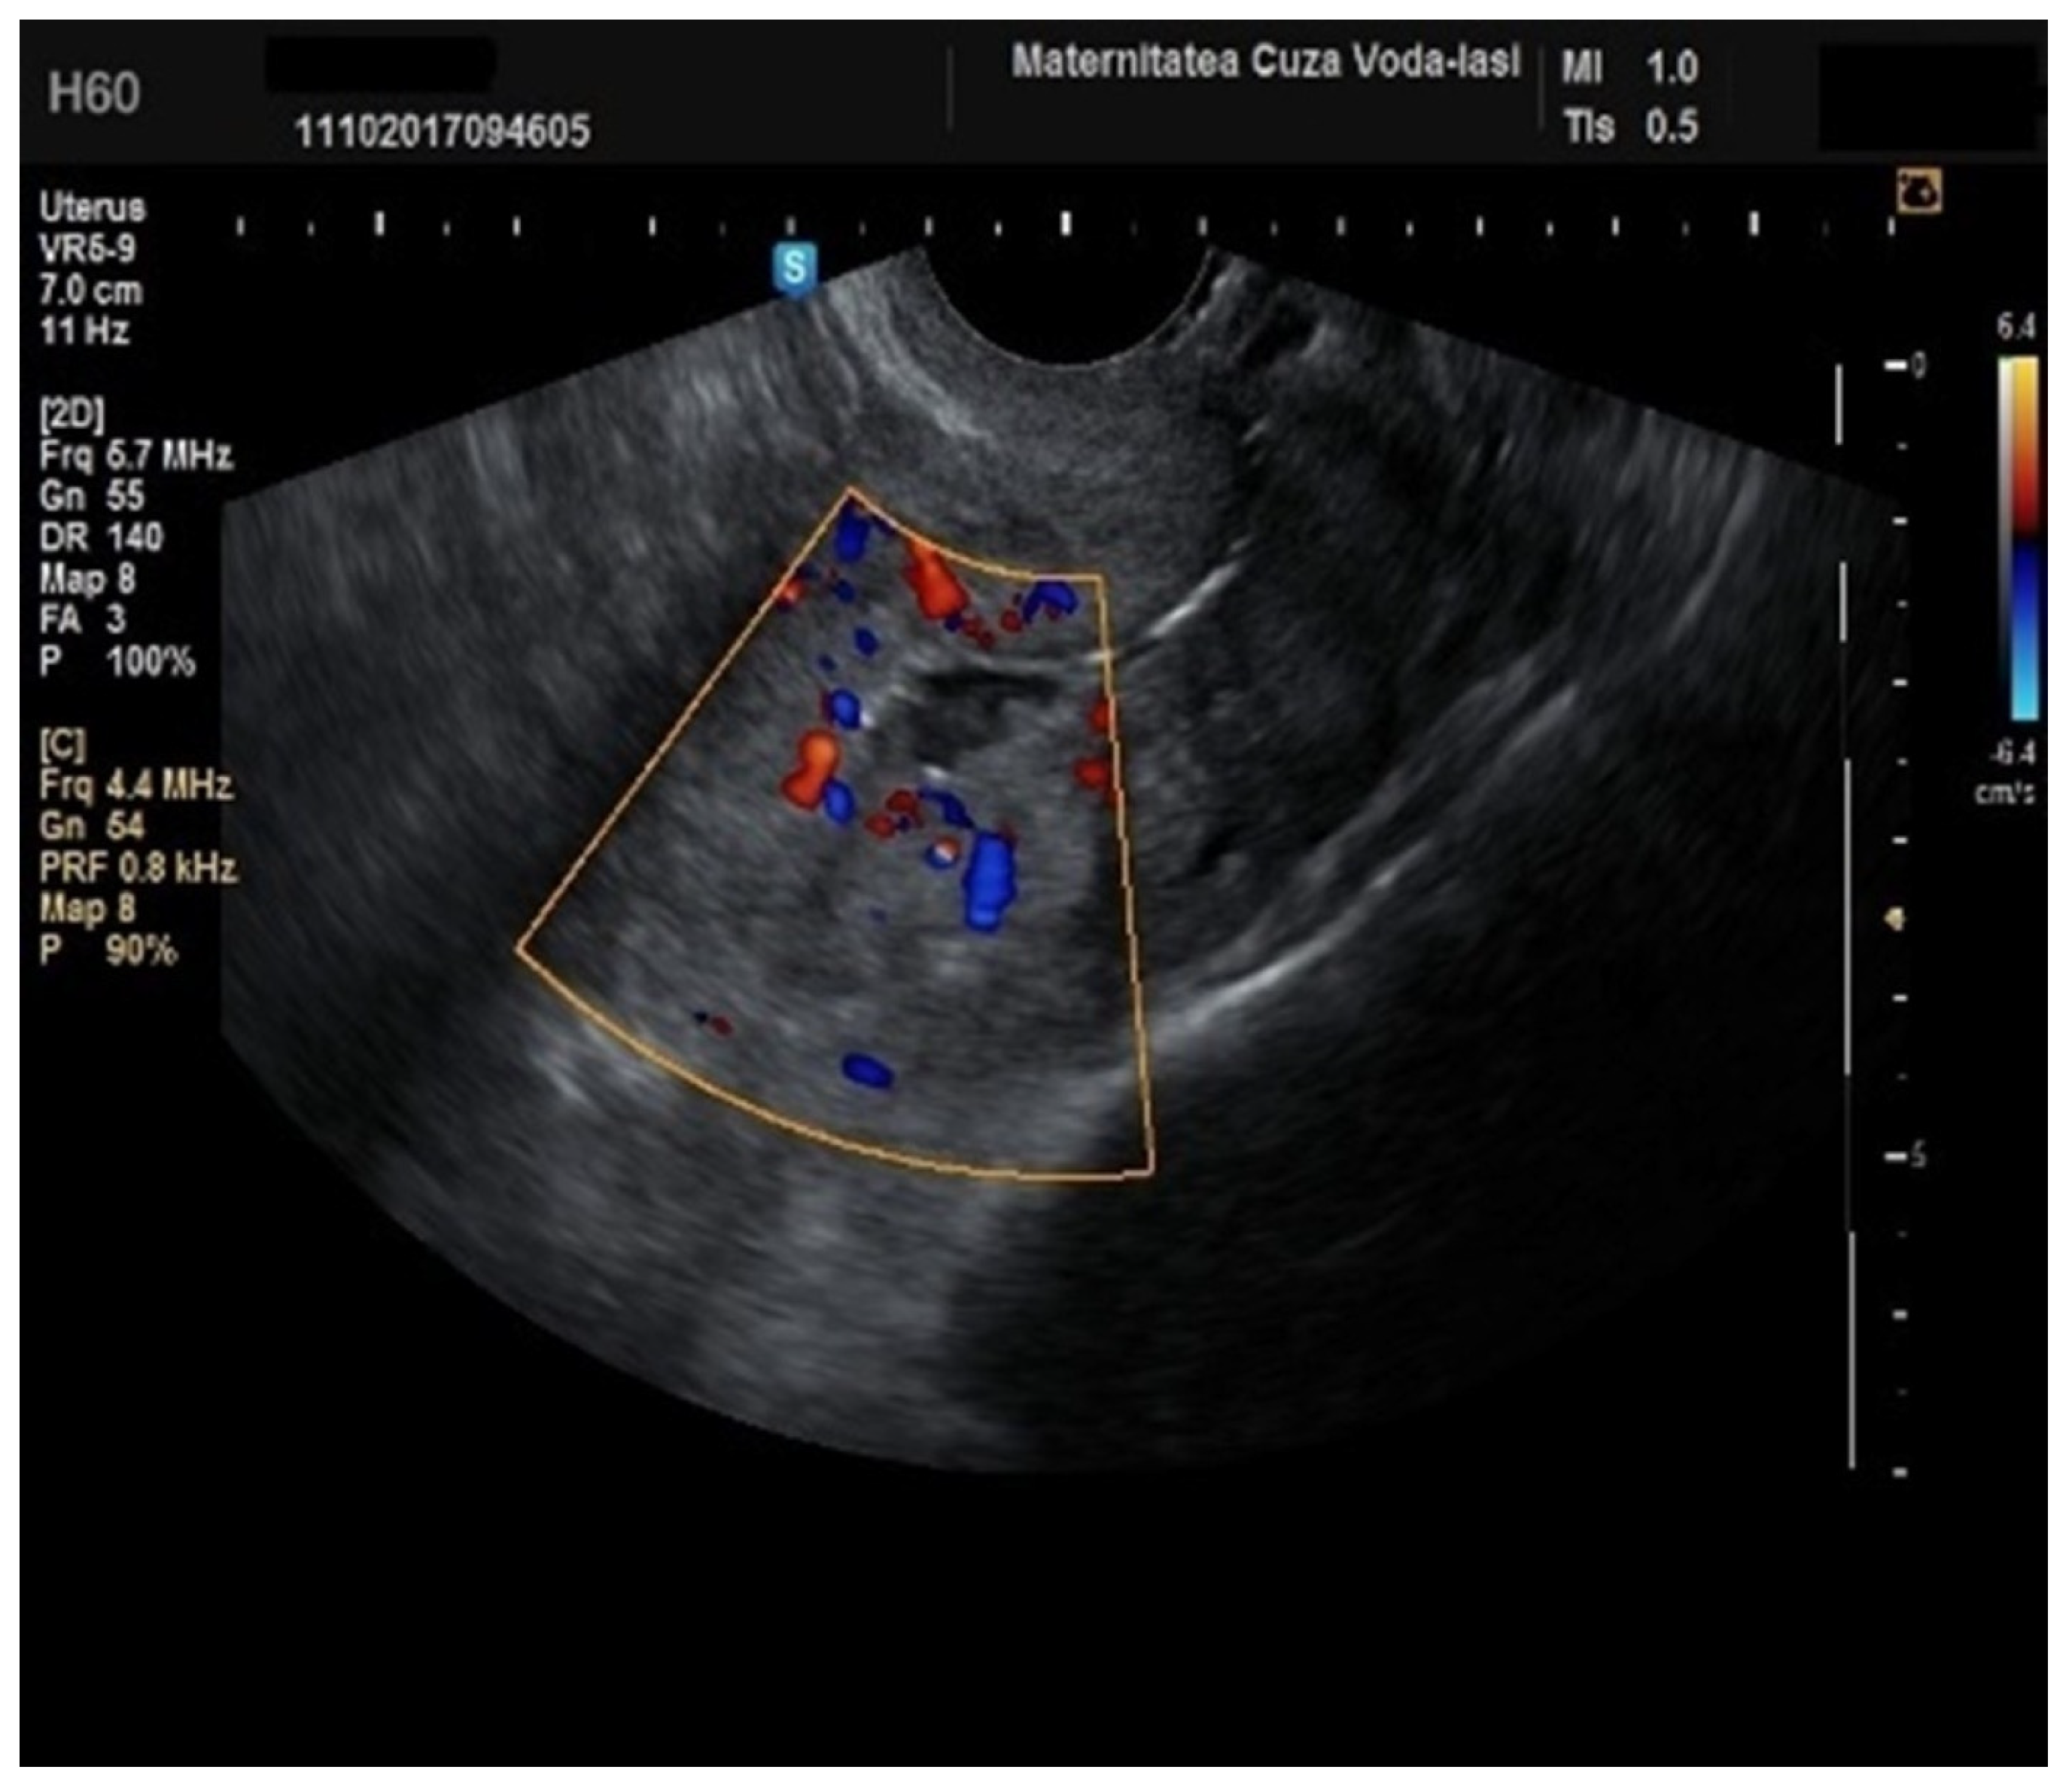

Regarding the color Doppler assessment, a vascular score of 1 usually excludes endometrial cancer, with a sensitivity of 87.5% and a specificity of 79% (Figure 8). This is due to the presence of a high number of newly formed vessels in malignant tumors (Figure 9).

Figure 9. Color Doppler vascular score 4 in endometrial cancer.